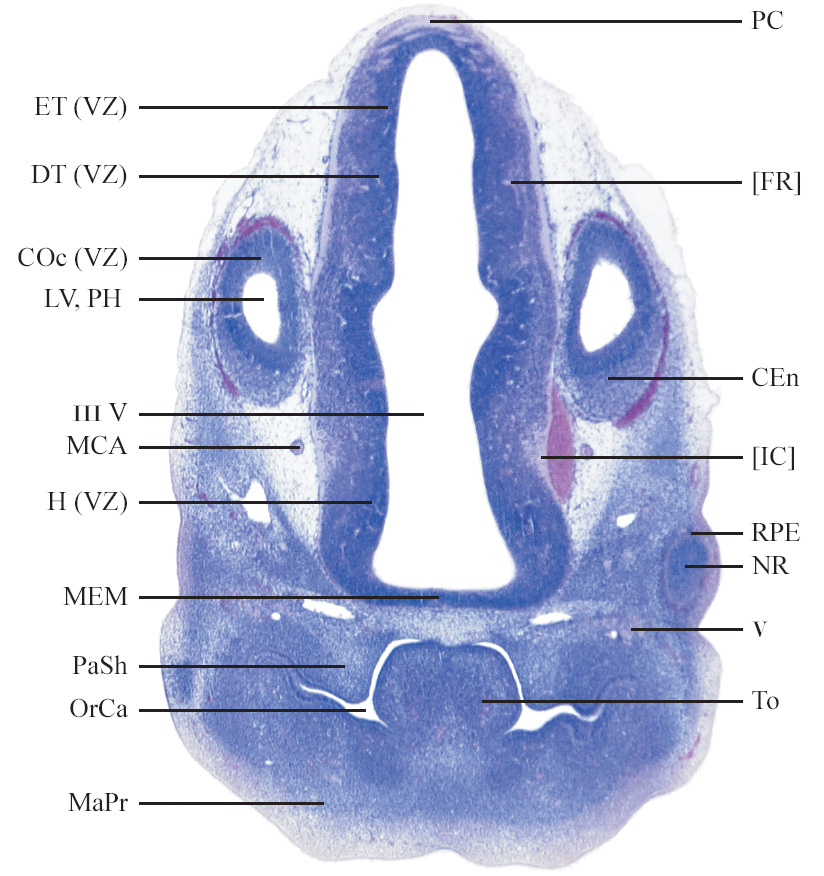

C57BL/6J GD12 Mouse Brain Atlas

Slides from U. Schambra, coronal cuts with slides at every 5th section, with a hematoxylin and eosin (H & E) stain

Currently on section 105.